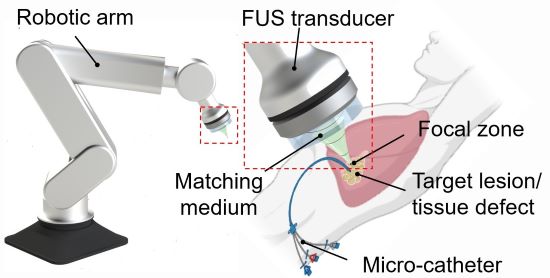

A fully autonomous robotic ultrasound system for thyroid scanning

Current thyroid ultrasounds rely heavily on the experience and skills of the sonographer and of the radiologist, and the process is physically and cognitively exhausting. Here, the authors show a fully autonomous robotic ultrasound system, which is able to scan thyroid regions without human assistance and identify malignant nodules.